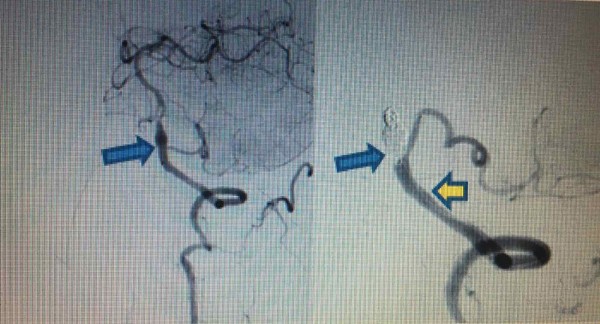

Chiều 4/4/2020, ông Tr. Q. T. (57 tuổi, ở Hà Nội) phải nhập viện do đột quỵ não tái phát. Kết quả chụp CT mạch máu não cho thấy ông T. bị phình hình thoi do bóc tách động mạch đốt sống trái lan vào gốc PICA trái. Kíp can thiệp bệnh viện Vinmec Times City đã tiến hành can thiệp đặt stent loại bỏ phình mạch não.

Trước đó, lần đột quỵ đầu tiên của ông T. xảy ra vào chiều ngày 20/3/2020 và đã được cấp cứu kịp thời tại BV Vinmec Times City với chẩn đoán tắc hoàn toàn động mạch đốt sống trái, tắc gốc PICA cùng bên gây nhồi máu cấp tính thùy nhộng và bán cầu tiểu não trái. Lúc đó, người bệnh đã được các bác sĩ chỉ định lấy huyết khối cơ học động mạch não DSA ở giờ thứ 3.

“Ưu tiên trong lúc đó là giải quyết phần “ngọn” để cứu tính mạng người bệnh, bởi thời gian can thiệp quá dài có thể quá sức chịu đựng của người bệnh trong bối cảnh đó. Do đó, trong hơn 1h đồng hồ, kíp can thiệp đã tiến hành hút huyết khối, nong bóng qua chỗ hẹp bóc tách và gốc PICA trái để khơi thông được mạch đang bị tắc nghẽn” - ThS.BS Vũ Huy Hoàng, Khoa Chẩn đoán hình ảnh, Bệnh viện Vinmec Times City, người trực tiếp can thiệp cho ông T. chia sẻ.